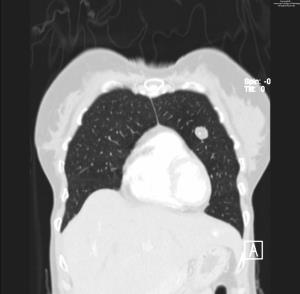

Read the Bulletin » Read the JACRTest your clinical knowledge with the daily Case in Point program, which gives you the opportunity each weekday to work through a subspecialty case.